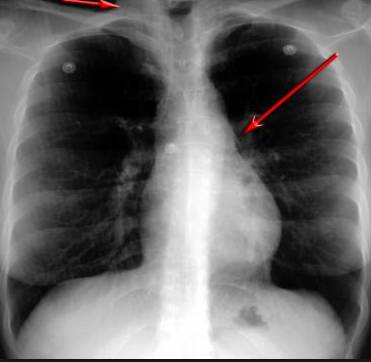

澳洲醫療新發明!顛覆傳統胸透和CT!世界首臺醫學4D動態掃描儀,直接透視器官!

并且,因為呼吸系統結構復雜,在體檢時醫生很難通過一種檢測手段,判定早期患者的病情。

整個肺部看得清清楚楚!

使用這臺掃描儀,將直接把器官變成3D圖形!細微的毛細血管,幾毫米大的肺泡和支氣管,都將能看的一清二楚!

你的每一個氣泡,每一段支氣管,哪兒有病變都清清楚楚的將展示在醫生面前!

不同于CT掃描,需要從同一角度,拍下無數張器官二維圖,從而搭建3D器官結構圖那般費時費力。

4D掃描儀將直接從不同角度,同時對人體器官進行掃描,然后通過計算機算法進行快速成像。CT需要花幾小時才能完成的工作,

4D掃描將在幾秒內完成!

當大家還在為B超、X光、CT哪個輻射更少而爭論不休時,這臺新機器已經比現有掃描儀少20%的輻射